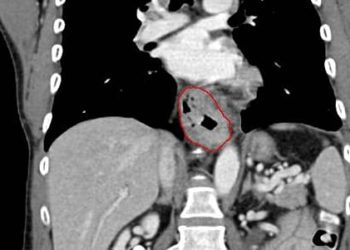

This [prospective cohort] study investigated the effectiveness of magnetic sphincter augmentation in treating gastroesophageal reflux disease (GERD). The study followed 100 GERD patients who received laparoscopic implantation of a circular magnetic device. The device augments the lower esophageal sphincter and reduces acid reflux. The study focuses on the clinical benefits of this procedure, and no control group was established.

In terms of clinical efficacy, the procedure achieved a reduction of at least 50% esophageal acid exposure in 64% of patients (95% confidence interval [CI], 54 to 73). Additionally, the procedure achieved a reduction of 50% or more in the average daily dose of proton-pump inhibitors (PPIs) in 93% of patients (95% CI, 86 to 97).

In terms of quality of life impact, the study used GERD-Health-Related Quality of Life questionnaire to quantify improvements, with a reduction of score indicating improvement. 92% (95% CI, 85 to 97) of patients had a 50% reduction in score.

In sum: This study demonstrated that magnetic augmentation of the lower esophageal sphincter could be an effective treatment for GERD. The study demonstrated both clinical reduction in acid reflux reduction and improvements in quality of life.

Due to the link between esophageal acid damage and cancer, magnetic sphincter augmentation is a novel treatment option that could reduce long term complications of GERD in patients that had only partial response to PPIs and cannot tolerate fundoplication or other surgeries.